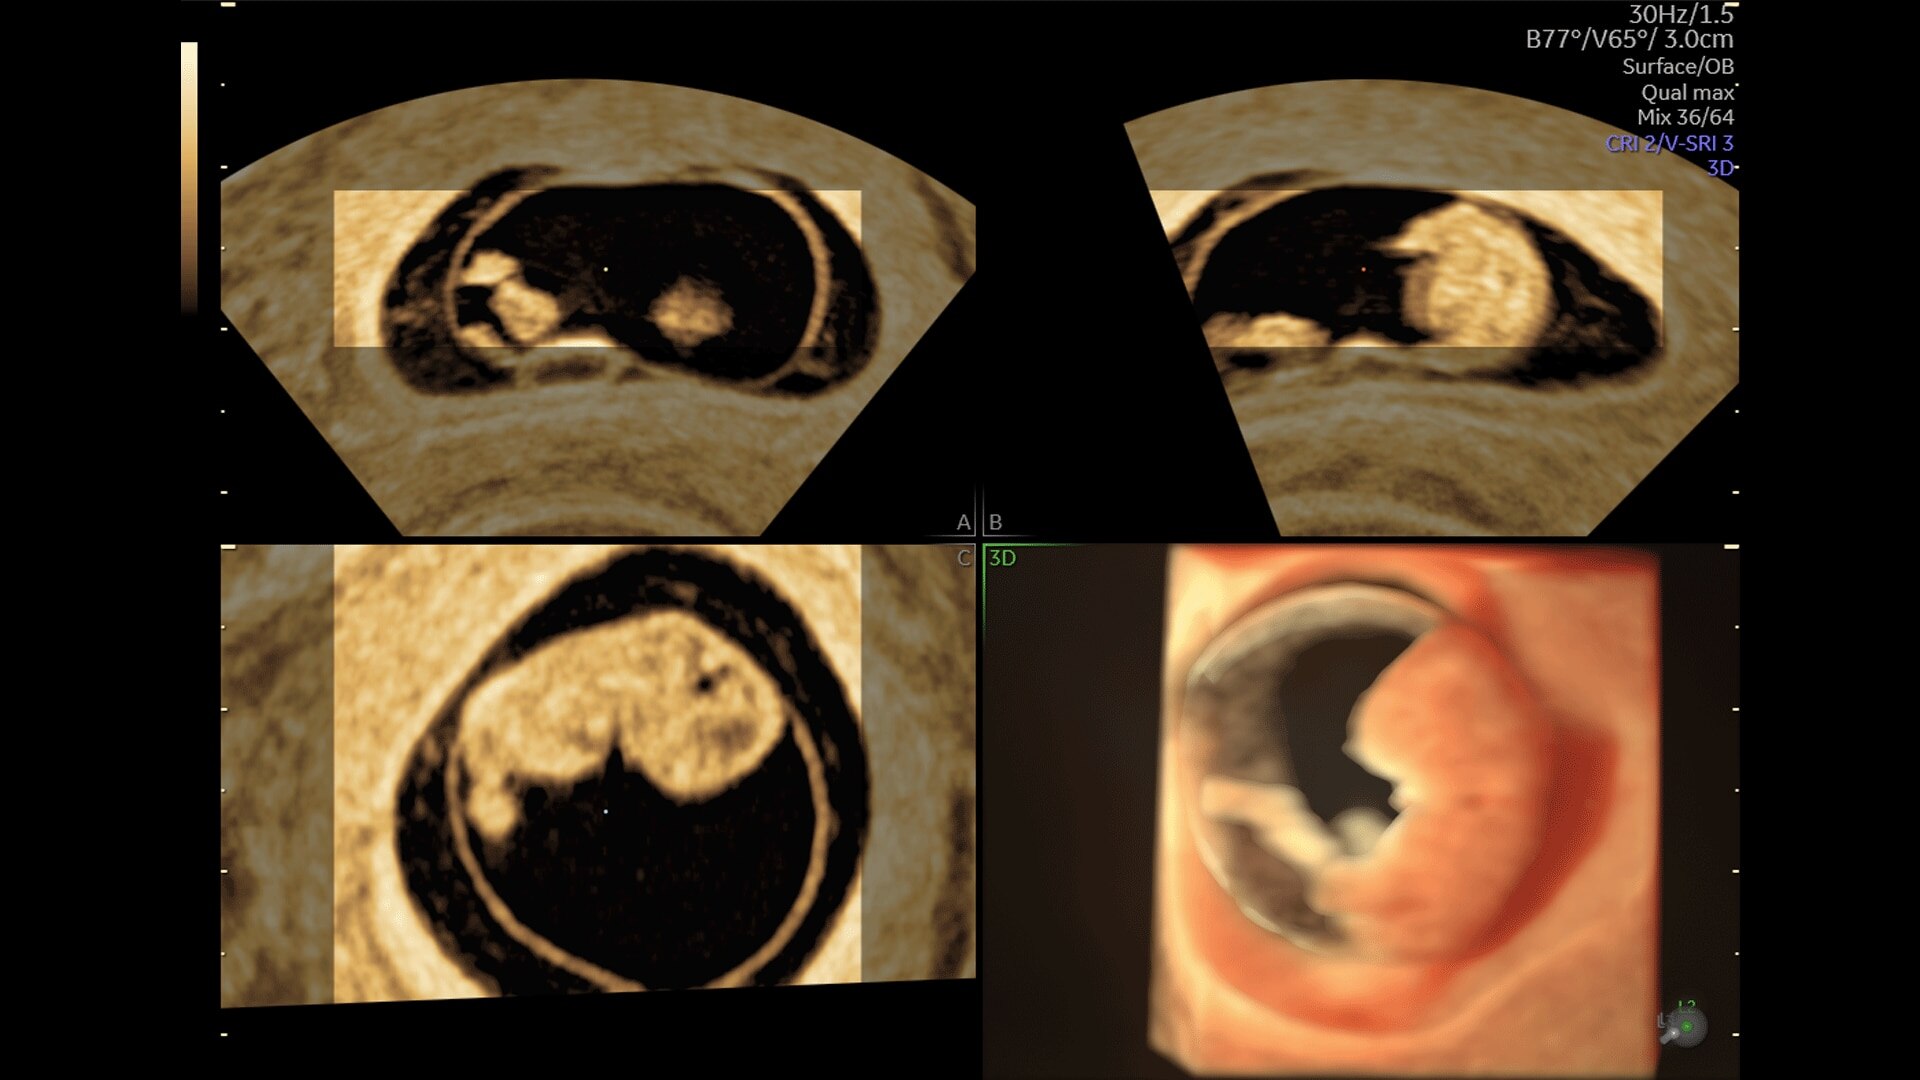

Generate spectacular 2D/3D and color Doppler images with increased penetration and stunning clarity, to help visualize critical details needed for diagnostic assurance. The Lyric Architecture unlocks new imaging and processing power to expand your imaging capabilities for years to come